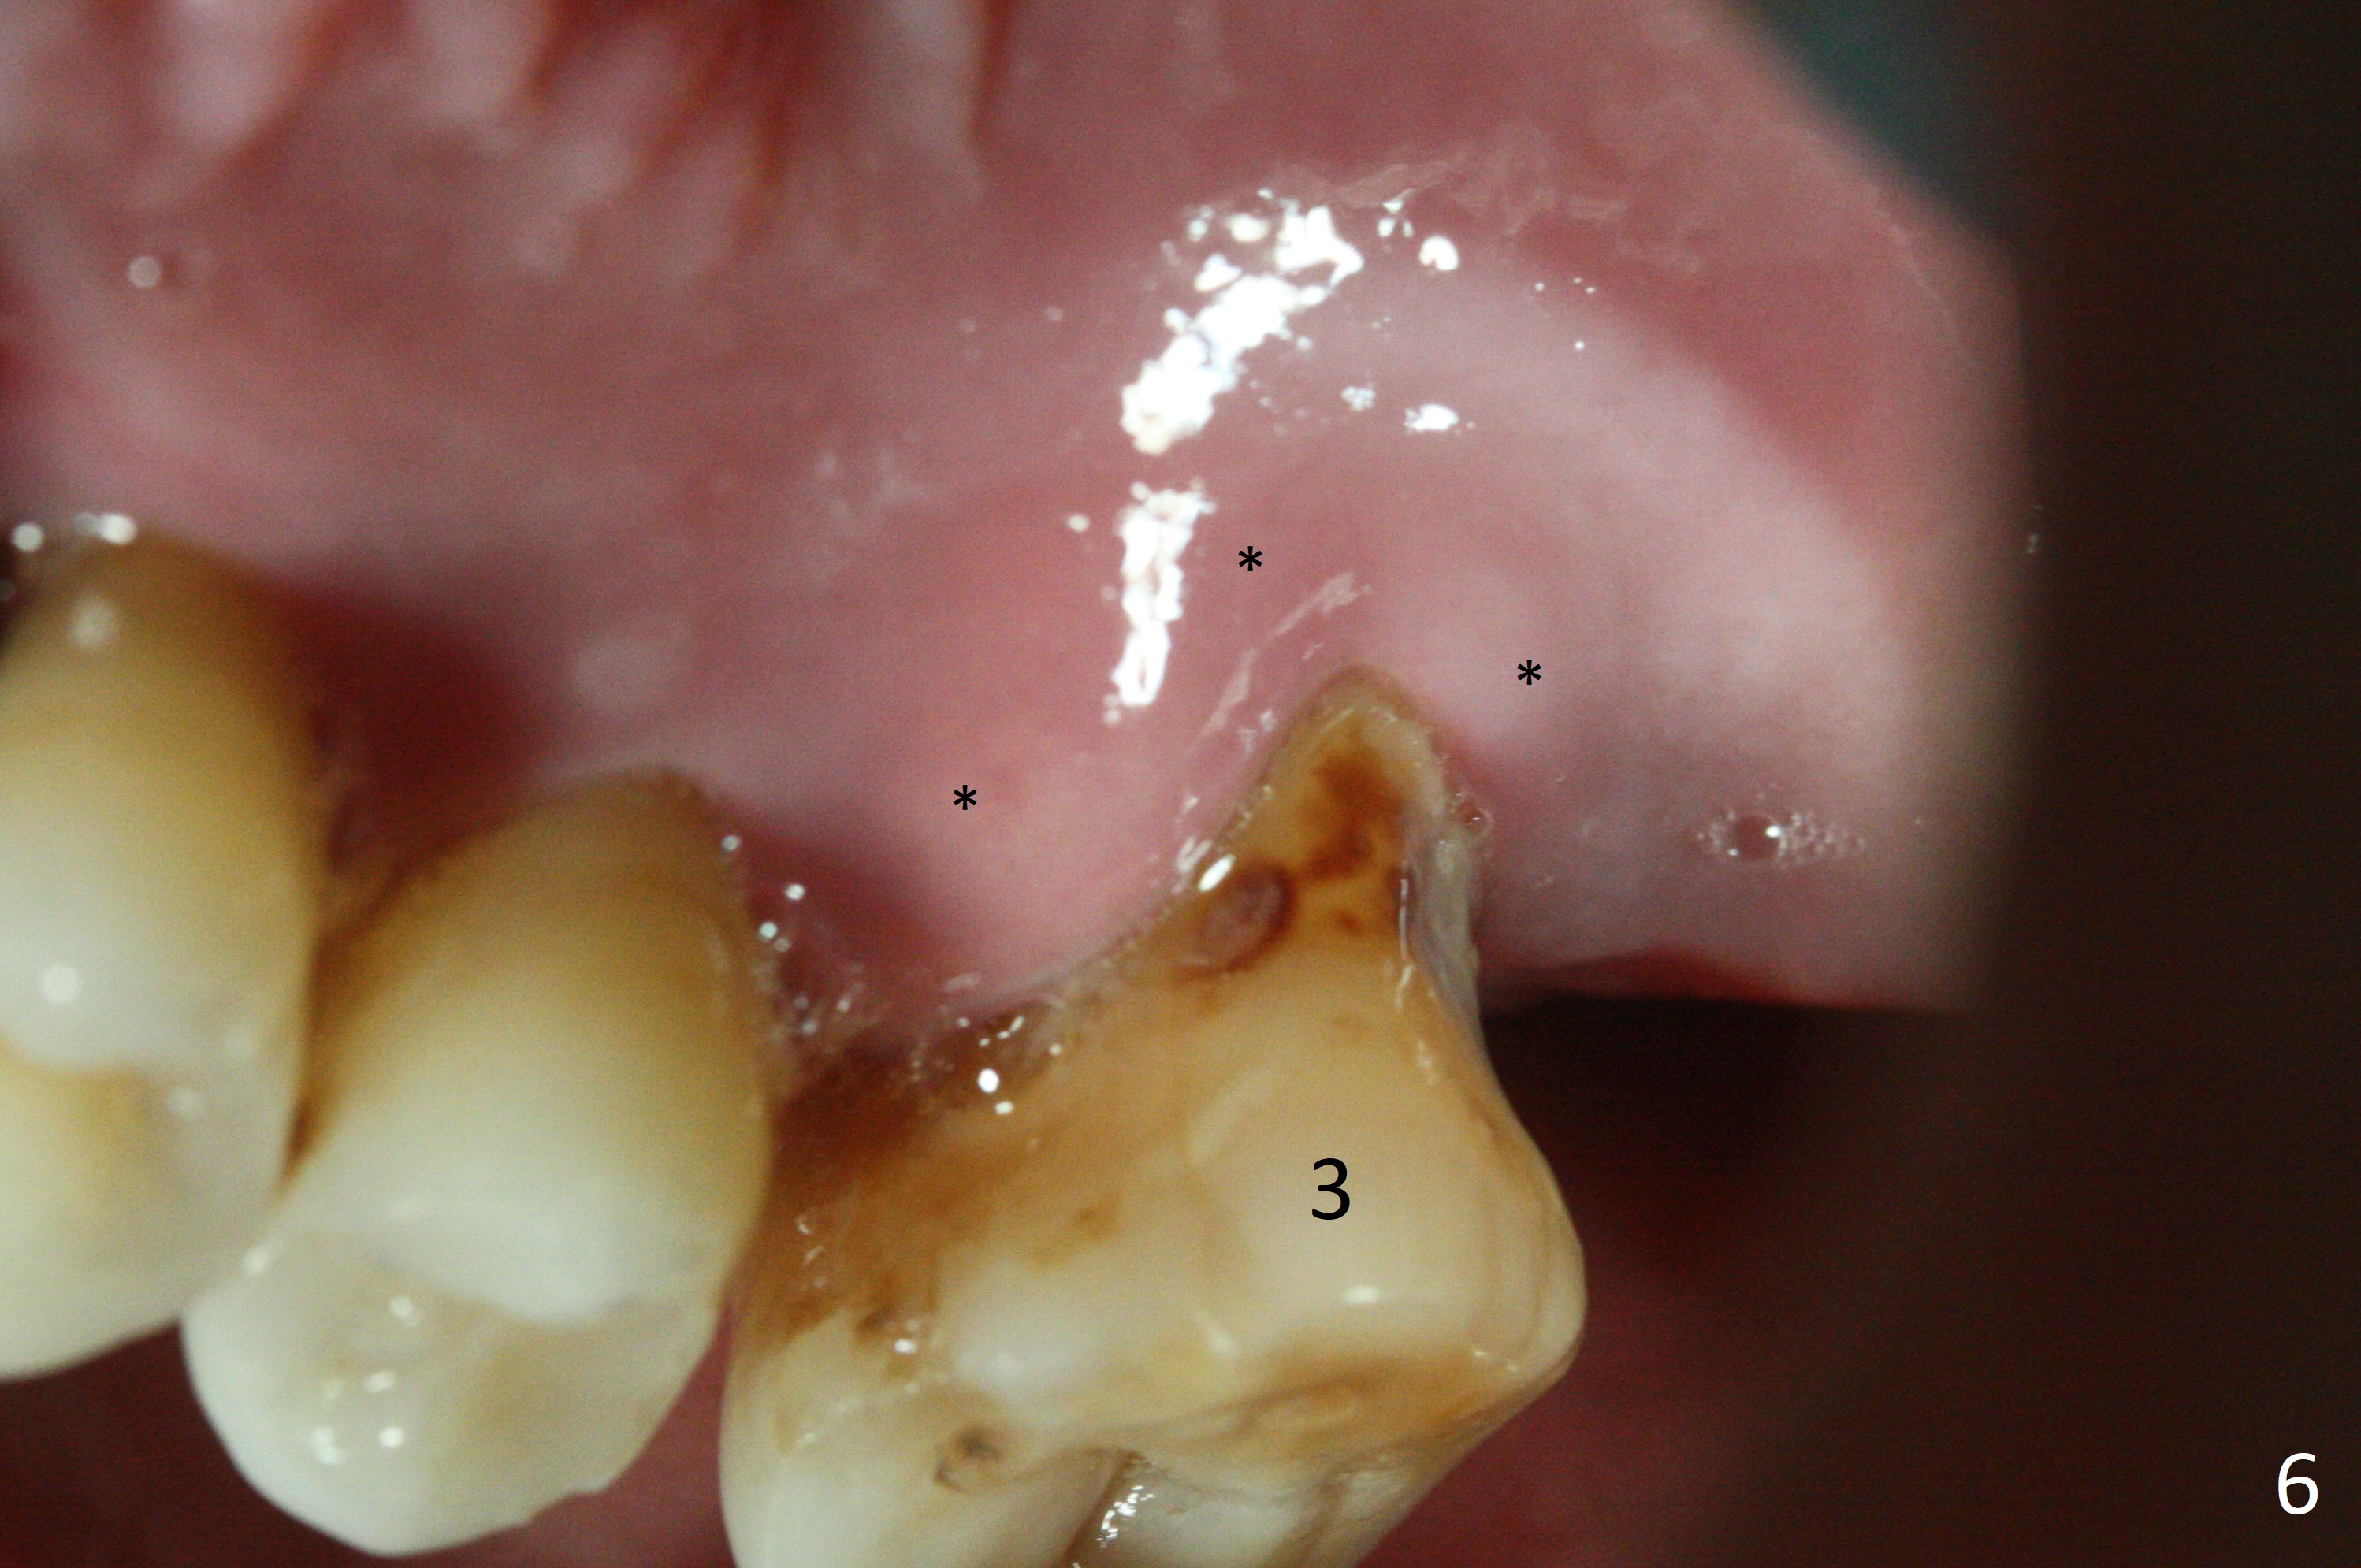

A 44-year-old man requests an implant at #3 because of mobility. It appears that the bone height decreases from 6 mm (Fig.1,2: 3 years ago) to 4 mm (Fig.3,4, recently). After extraction and Clindamycin treatment, take PVS impression of the socket. Use initial drill with drill stopper of 3 mm and round burs with stoppers from 4 to 5 mm. If the buccal (B) and palatal (P) plate defect is severe, use a regular implant. Otherwise use an extra wide one. The advantage of the latter is length as short as 6 mm vs. 8 mm for the regular one. For the latter, 2 mm of the implant will be in the sinus (Fig.4 red box), 4 mm in bone (pink box) and 2 mm in the socket (orange box; to be surrounded by bone graft). Since the gingiva is 6 mm (Fig.4 green box), an abutment with 6 mm cuff should be chosen. To reduce occlusal interference, select abutment height 4 mm.

Recently periodontal abscess occurs with purulent discharge from the buccal sulcus (Fig.5 *) and palatal gingiva erythema and edema (Fig.6 *). The buccal and palatal plates are most likely defective. A small diameter implant should be placed. The infection at #3 may be the cause of failure of implant at #31 (redo).